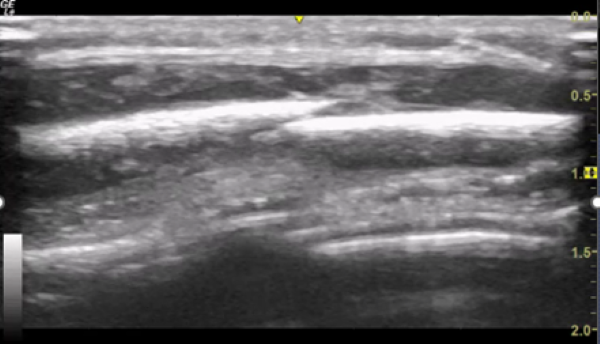

Figure 1. POCUS of parietal skull showing fracture

You explain to the parents that these images are consistent with a skull fracture and ask how this may have happened in a child not yet independently mobile.